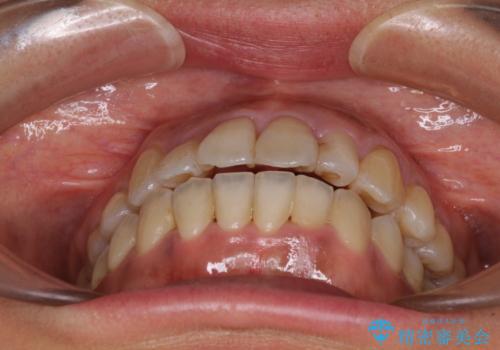

狭い上顎骨を拡大 著しい叢生を抜歯矯正で改善

- 上顎の著しい叢生と奥歯の咬みにくさを気にして来院された患者様です。

骨格的に上顎は狭く、下顎は右側にシフトしていたため、右側臼歯はクロスバイトとなっていました。

上顎骨を急速拡大装置により拡大し、ワイヤー装置による抜歯矯正治療を行うこととしました。